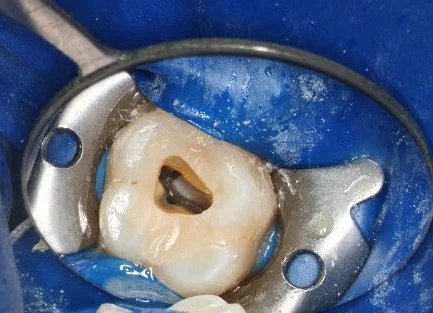

The centerpiece of any modern endodontic office should be the dental(surgical) operating microscope. This technology has been available for sometime, and its utilization has steadily increased over the years. Without clear and consistent visualization of the internal anatomy of tooth root, it is impossible to properly identify and clean the root canals. At South Mississippi Endodontics we utilize the microscope during all procedures on all patients. The picture to the right illustrates the improved visibility the microscope provides.

This recently coined term refers to a concept of providing endodontic therapy while maintaining the maximal amount of tooth structure. Traditionally, dentists and endodontists were trained to open the roof of the tooth chamber to provide "straight line access" to all canals - which can significantly weaken the tooth. This was necessary prior to the advent of the modern endodontic armamentarium. The improved visualization and ergonomics provided by the microscope and the flexibility of today's rotary endodontic files allows us complete ideal endodontic therapy while minimizing the amount to coronal tooth structure removal. This minimalist idea can be extended to the root canals themselves. Most recent endodontic literature has been geared toward a "bigger is better" idea of cleaning and shaping. While there is little doubt that this methodology will lead to a "cleaner" canal, what is less clear is whether this "increased cleanliness" improves the long-term success. Interesting, endodontic success rates have not risen significantly in recent years. This would at least raise the possibility that "bigger/cleaner" may not matter in the way that we have been trained. Our goal is simply to treat the patient's symptoms/disease while respecting the dentin (especially the pericervical dentin). This method does not create "the look" of the dramatically tapered root canal preparations that are seen in most of today's endodontic marketing material; however, it should lead to improved long-term success and tooth retention. The cases below illustrate how this concept has been implemented into our practice.